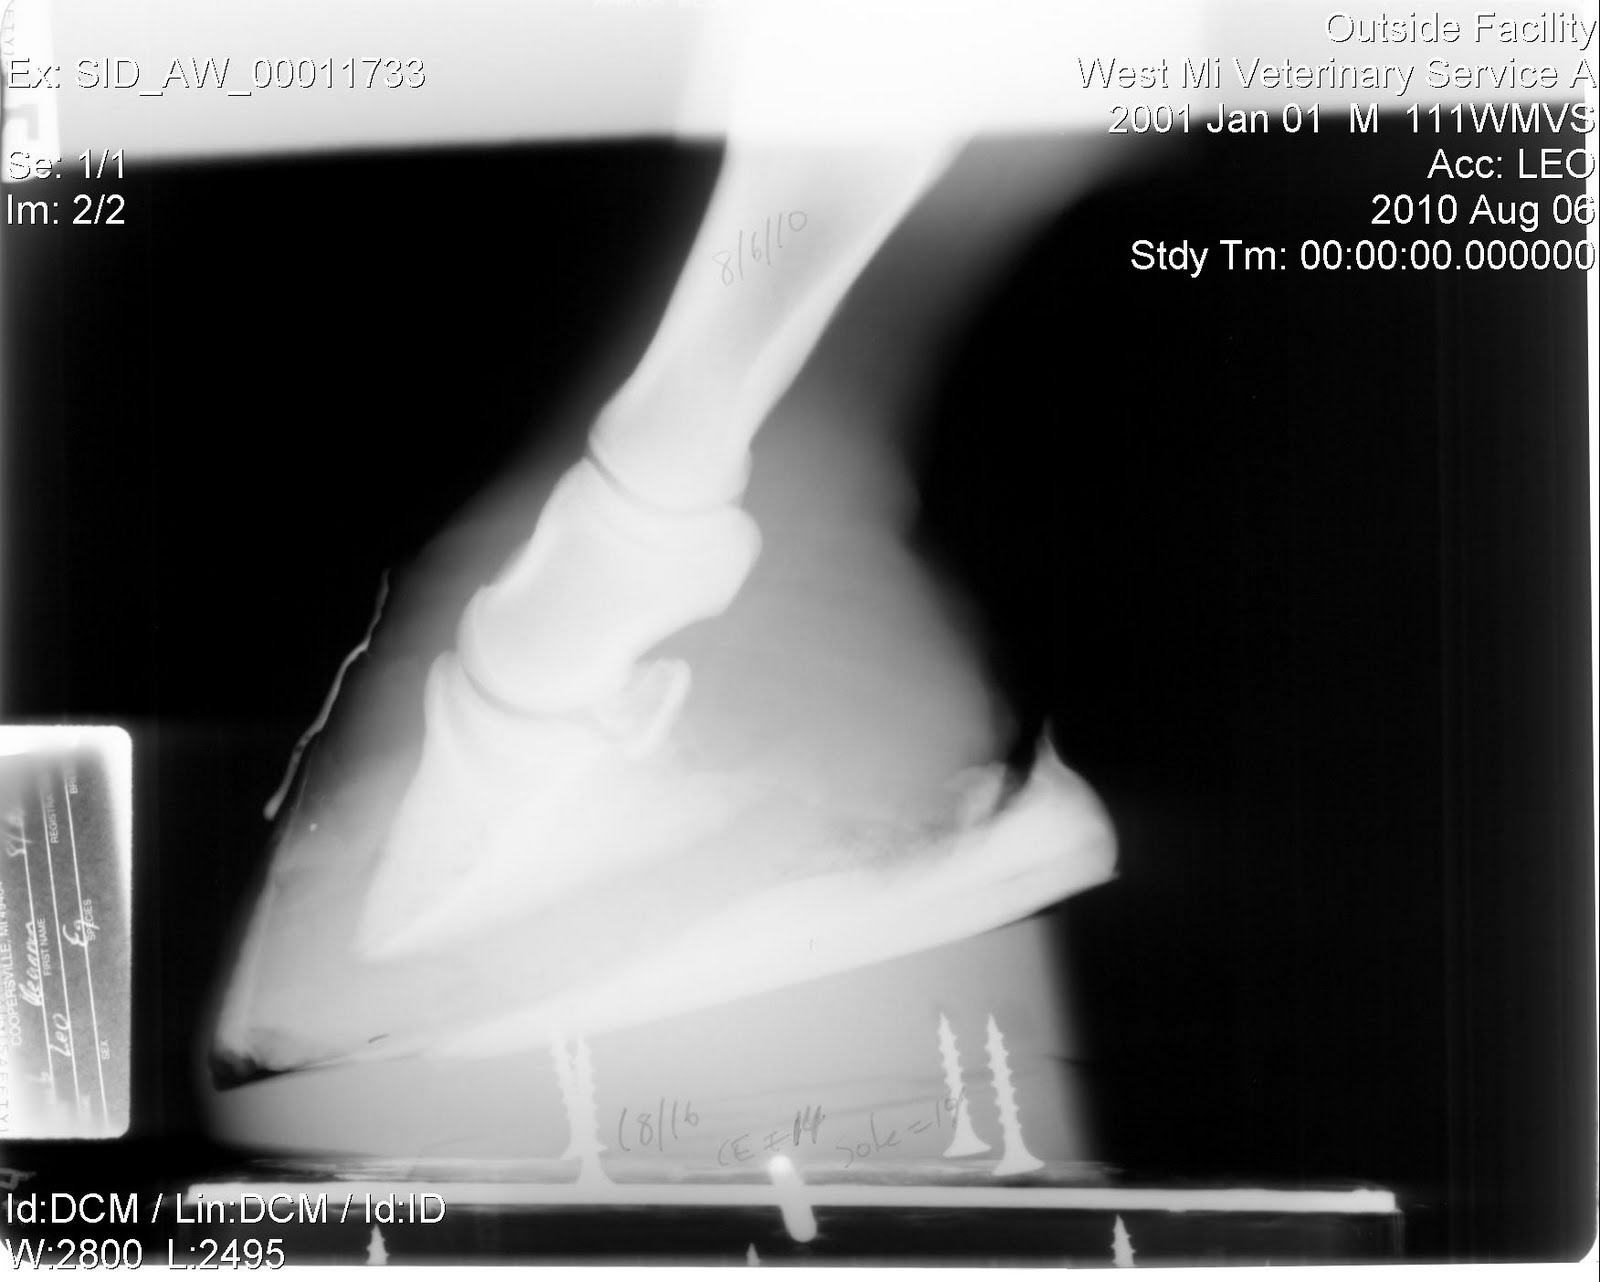

Horse Founder X Rays . founder in horses, also called laminitis, is the profound swelling and pain in the hoof when. radiographic studies are an essential. This can reveal underlying causes like metabolic disorders that can predispose a horse to founder. These can show any rotation or sinking of the coffin bone inside the hoof, providing a clear picture of the severity of the founder.

radiographic studies are an essential. These can show any rotation or sinking of the coffin bone inside the hoof, providing a clear picture of the severity of the founder. founder in horses, also called laminitis, is the profound swelling and pain in the hoof when. This can reveal underlying causes like metabolic disorders that can predispose a horse to founder.

Founder Info for Horse Owners! Leo's Radiographs (aka xrays) Horse Founder X Rays These can show any rotation or sinking of the coffin bone inside the hoof, providing a clear picture of the severity of the founder. founder in horses, also called laminitis, is the profound swelling and pain in the hoof when. This can reveal underlying causes like metabolic disorders that can predispose a horse to founder. radiographic studies are. Horse Founder X Rays.

Founder Info for Horse Owners! Leo's Radiographs (aka xrays) Horse Founder X Rays This can reveal underlying causes like metabolic disorders that can predispose a horse to founder. founder in horses, also called laminitis, is the profound swelling and pain in the hoof when. These can show any rotation or sinking of the coffin bone inside the hoof, providing a clear picture of the severity of the founder. radiographic studies are. Horse Founder X Rays.

Founder Info for Horse Owners! Leo's Radiographs (aka xrays) Horse Founder X Rays radiographic studies are an essential. This can reveal underlying causes like metabolic disorders that can predispose a horse to founder. These can show any rotation or sinking of the coffin bone inside the hoof, providing a clear picture of the severity of the founder. founder in horses, also called laminitis, is the profound swelling and pain in the. Horse Founder X Rays.